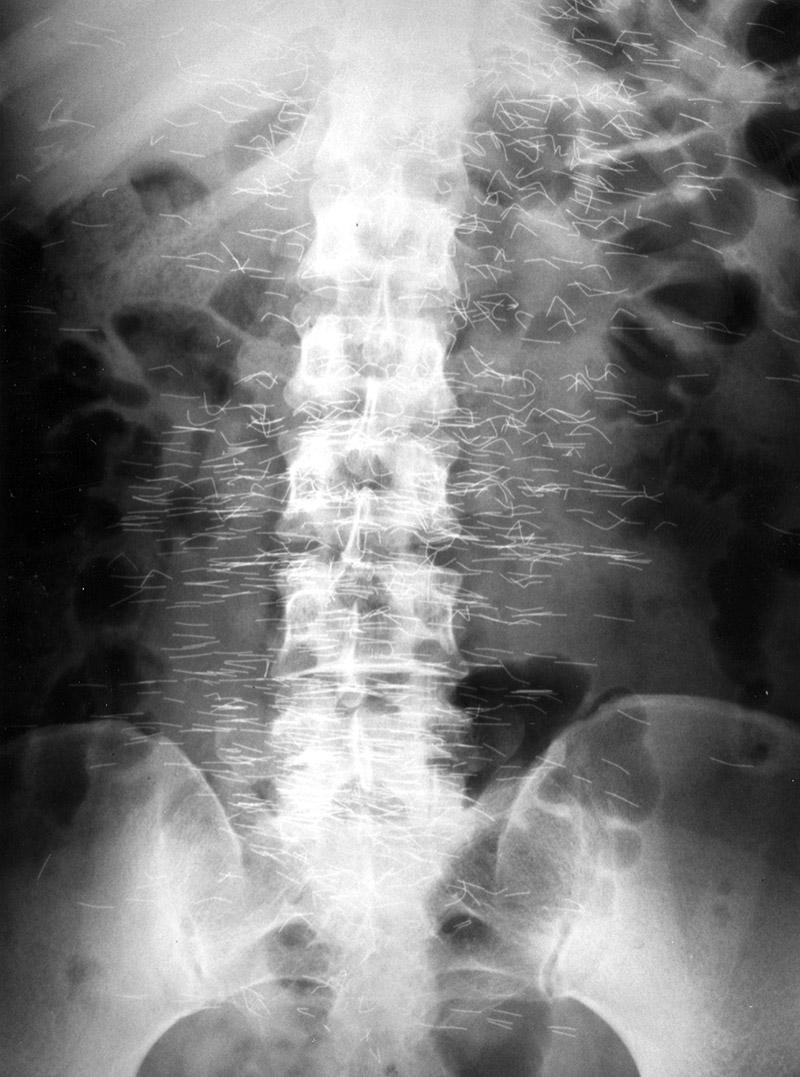

Some individuals who practice sorcery or wizardry may insert wires, paper clips, or other objects in themselves to ward off evil spells (Desrentes, 1990). Patients undergoing instrumentation or surgery may experience an iatrogenic injury involving foreign material inserted into the body (Sturdy, 1967; Rappaport, 1990; Hunter, 2010). Most acupuncture needles are temporarily inserted into the subcutaneous tissues of the body, but they may be deliberately or accidentally left in place (figure: acupuncture needles) (Imray, 1975; Schatz, 1976; Glauten, 1988; Saenz, 1978; Behrstock, 1974).

Susuk charm needles (Malaysian charm needles) are metallic talismans inserted subcutaneously to ward off injury or to treat a present condition. This practice is most common in Southeast Asia and is hidden in the sense that the patient does not generally reveal the presence of sucn foreign bodies or might not even know they are present having received them as a child. The susuk charms are like pins or needles roughly 0.5 mm in diameter and between 0.5 to 1.0 cm in length. They are usually mostly composed of gold and are considered safe for MRI (Martin, 2019). The most common site of insertion is the facial region.

21 year-old man who injected himself with metallic mercury. There are mercury emboli to the lungs and metallic mercury is evident in the antecubital fossa of the left elbow. (Figures courtesy of Charles A. Rohrmann, Jr, MD. They were originally printed in Peterson, 1980). Trick or treat candy. There are no hidden needles or razor blades. The candy and the apple (round density) where eaten with much enjoyment. From Hunter, 1994